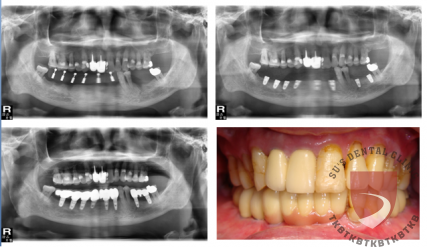

全口重建劉xx

成效因人而異,須遵從專業醫師指引